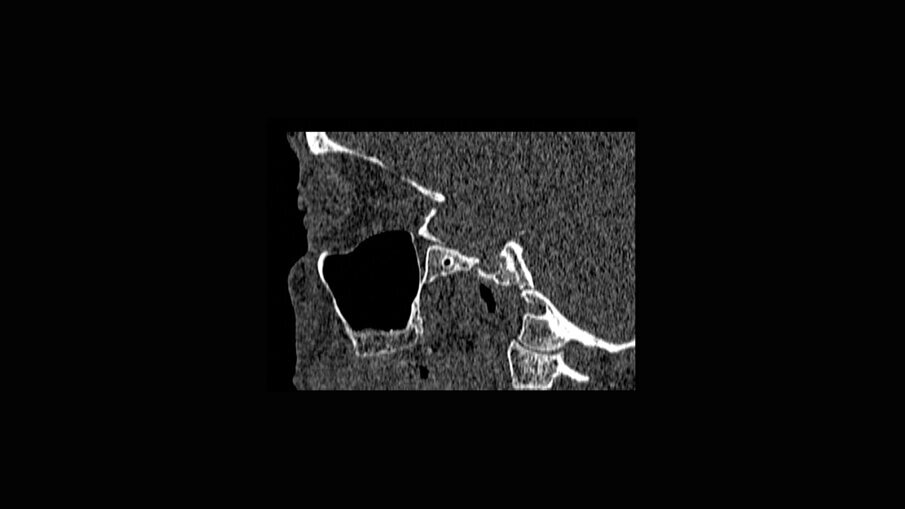

- pianificazione chirurgica della riabilitazione con valutazioni anatomiche, TC Cone-Beam, stereolitografia (SLA), funzionale al progetto protesico;

È presentata una riabilitazione con 4 impianti zigomatici (QUAD) in paziente con grave atrofia del mascellare. In questo caso la protesi con carico funzionale è stata consegnata alla paziente dopo 72 ore. Nelle immagini 1-4 viene mostrata la stereolitografia e la TC della paziente, mentre nelle immagini 5-7 viene mostrata la situazione iniziale e finale della paziente.